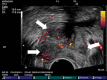

Transrectal ultrasound (TRUS) was first developed in the 1970s. TRUS-guided biopsy, under local anaesthetic and prophylactic antibiotics, is now the most widely accepted method to diagnose prostate cancer. However, the sensitivity and specificity of greyscale TRUS in the detection of prostate cancer is low. Prostate cancer most commonly appears as a hypoechoic focal lesion in the peripheral zone on TRUS but the appearances are variable with considerable overlap with benign lesions. Because of the low accuracy of greyscale TRUS, TRUS-guided biopsies have become established in the acquisition of systematic biopsies from standard locations. The number of systematic biopsies has increased over the years, with 10-12 cores currently accepted as the minimum standard. This article describes the technique of TRUS and biopsy and its complications. Novel modalities including contrast-enhanced modes and elastography as well as fusion techniques for increasing the sensitivity of TRUS-guided prostate-targeted biopsies are discussed along with their role in the diagnosis and management of prostate cancer.